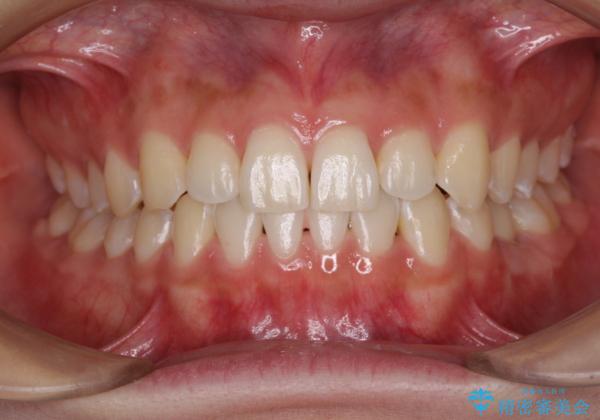

- 前歯の叢生と、奥歯の咬み合わせの悪さを気にして来院された患者様です。

左下には後続永久歯の欠損した乳歯が残存しており、叢生を相まって咬合関係が乱れていました。

乳歯は抜歯し、インビザラインにて矯正治療を行いながら、並行してインプラントによる補綴治療を行うこととしました。

矯正治療が終わるタイミングに合わせてインプラントの埋入を行っていたので、矯正治療を終了すると同時にセラミック補綴治療を行えました。

短期間でしっかりと治療を終えることができました。